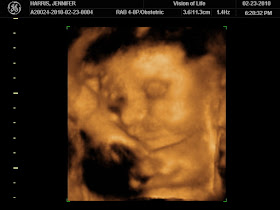

February - We see Owen in 4D for the first time!!